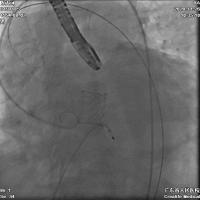

术中建立双侧股动脉入路,以右股动脉为主,送入导丝顺利跨瓣进入左室,先行球囊预扩张,处理主动脉瓣环钙化;后续沿已建立的导丝路径,送入Edwards Sapien 3球囊扩张式主动脉瓣膜置换系统,在推送的过程中,一边调弯一边缓慢推送,保证安全过弓并成功完成跨瓣。

随后将Edwards Sapien 3瓣膜精确定位至预期位置,以180次/min快速起搏,保证1:1夺获,使收缩压降至50 mmHg,迅速释放瓣膜,整个过程一气呵成。

瓣膜植入后,即刻跨瓣压差几乎为零,无残余瓣周漏,顺利结束手术。